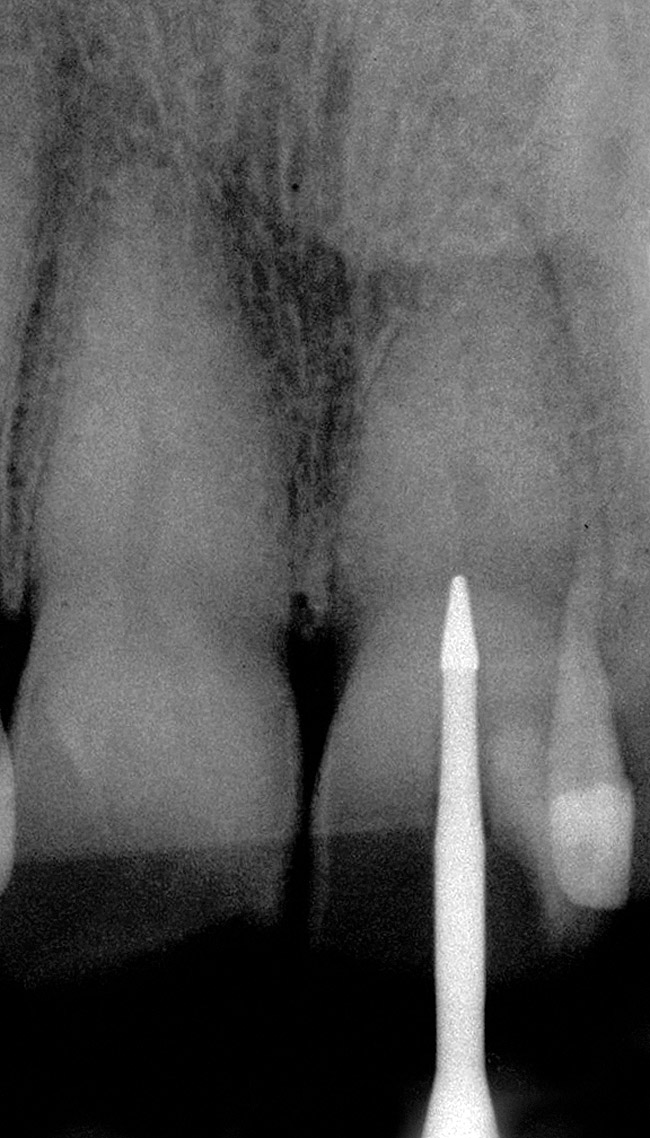

Figure 1 shows a radiograph of a typical maxillary first molar. Upon extraction, the apical anatomy was immediately studied and photographed under a global microscope ( Figure 2, Figure 3, Figure 4, Figure 5 and Figure 6). That is a take-home lesson; the extracted teeth should be studied with loupes or microscopes. These photographs demonstrate an important lesson. The two-dimensional radiograph shows three roots. In reality, however, a significant percentage of maxillary first and third molars—80% in some studies—have four roots and four or more canals. 1,2 While the MB and MP (MB-2) roots are usually fused, their morphology is unique. For diagnostic, access, and shaping purposes, it is safer to think of them as separate roots. Wisdom teeth often exaggerate the anatomic features of first and second molars, and a significant percentage of maxillary third molars have four distinct roots. The author's personal bias is to consider most maxillary first the radiographic apex of the tooth. The use of the radiographic root apex for use as the reference point for measuring the apical extent of the root filling is the common standard, yet has been criticized because of the poor correlation between the location of this point and the actual canal foramen. 5 The illustrations used in advertising and manufacturer's "tip cards" only further the notion of simple foramen anatomy. While simple anatomy is often the case with incisor teeth, a quick perusal of the posterior teeth in Brown and Herbransen's Dental Anatomy & 3D Interactive Tooth Atlas demonstrates that a significant portion of the foramen exit short of the apex and have multiple foramina. 6 The same extracted tooth in Figure 2 demonstrates that the palatal foramen is more than a millimeter short of the radiographic apex. If this tooth were filled to the constriction, which for arguments sake is 0.75 mm from the foramen, a straight-on radiograph would depict the fill as being at least 2 mm "short."

Round burs have long been the bur of choice when accessing beyond the initial cavosurface access of the tooth. Because of the rounded end, round burs seem safer than other burs. The round bur is also the most commonly used for accessing and subsequently exploring the calcified tooth in pursuit of a tiny wisp of pulp. Clinicians' bias toward this bur stems from a combination of factors, but is based mostly on habit. There is a universal misconception that round burs in a latch grip cut slowly and safely, but neither is the case. The radiograph in Figure 7 shows the dangerous gouging that is common with both a round bur and the parallel-sided tunnel that a round bur eventually creates. Rather, a conical shape is preferred. In the hands of a skilled clinician, the conical shape is possible to cut with a series of decreasing diameter round burs, but an uphill battle must be waged against the cutting action of round burs. With the advent of modern bur shapes, this exceedingly difficult and dangerous task is no longer necessary ( Figure 8 and Figure 9). Conical-shaped burs allow the clinician to work with the bur to create the ideal access shape. A secondary benefit is that one or two conical carbide burs can replace seven or more traditional burs, such as multiple round burs and Gates-Glidden burs, for instance.